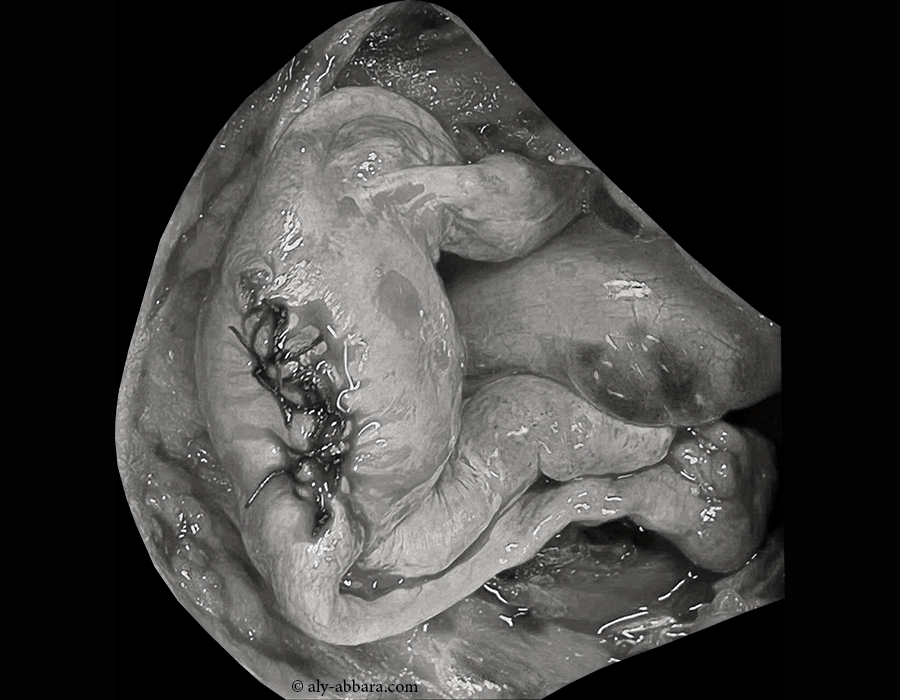

Images clinique montrant un utérus myomateux emplacement du site de la myomectomie réalisée sur un myome sous-séreux attaché au fond de l'utérus (myome classe 7 de la classification FIGO 2011). Image per-opératoire prise au 108ème jour du postpartum après un accouchement par césarienne au terme de 36,5 SA.

Au 108ème jour du postpartum, en per-opératoire (laparotomie), on constate qu'il s'agit d'un myome utérin évoluant à la surface extérieure du fond utérin et prenant l'aspect d'une formation kystique à paroi épaisse et adhérant partiellement à l'épiploon ; la vidange de cette masse permet l'extraction d'environ 950 ml de liquide brunâtre foncé.

La myomectomie totale est réalisée par un clivage limité à la surface extérieure du fond utérin avec une hystérotomie superficielle long d'environ 4 à 5 cm de longueur suturée par 5 points séparés.

La vascularisation très limitée de ce volumineux myome utérin fundique qui provient exclusivement de la partie superficielle du fond utérin peut expliquer son évolution particulière : nécrobiose aseptique massive et dégénérescence kystique .